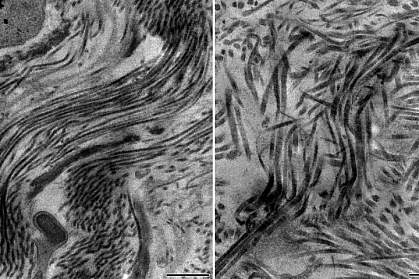

The collagen fibers in the scar tissue lacking type 5 collagen, instead of being neatly organized, were in disarray. Testing showed that this scar tissue was more flexible than normal, allowing it to expand. This explains why it is worse at helping the heart beat normally; it can’t properly transfer the forces needed in a beating heart.